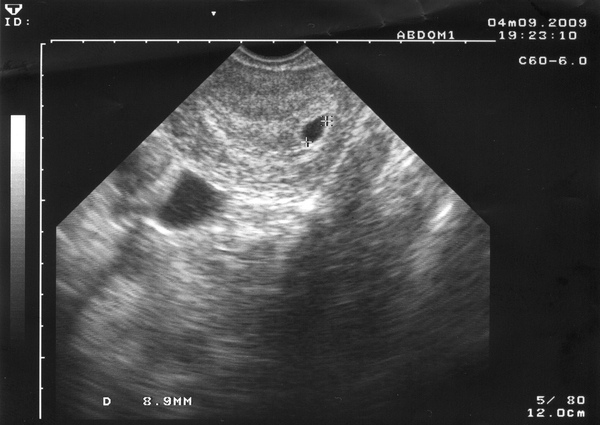

沒錯,我的第二個小孩來臨了.就在媽媽的肚子裡,第二天2009/3/31我的天使到了醫院再做一次確認,直到今天已經長大到了快一公分了哦.我試圖在網路上留下記錄,能在未來和我的天使及小天使一起找回當時悸動,讓這份記憶不要隨著時間而淡逝.就讓大家先看看上帝送的小天使,在他還沒變身成惡魔前